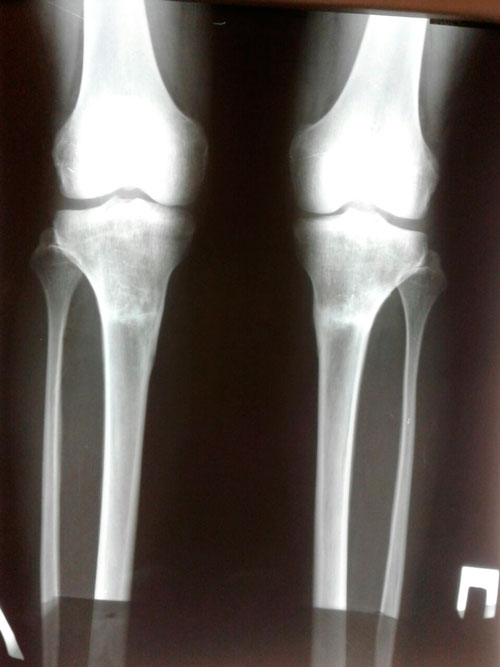

Исходник - 37 лет.

Дата операции 26.04.2017г.

РЕНТГЕН ДО ОПЕРАЦИИ